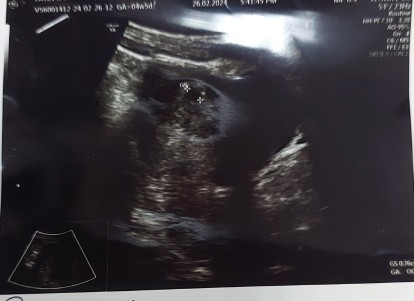

Jumpa DR di awal kehamilan

Hi.. Biasanya diawal kehakilan ni, Momies semua dating scan dgn dr di weeks yg keberapa ya?

Ye hai🥰 saya dtg scan swasta pada awal 5 w untuk tgok kedudukan kantung adakah ditempat yg betul atau tidak...sekiranya betul kedudukan kantung tu... saya akan ke klinik kesihatan terdekat untuk buka buku pink ... buku pink di antara seawal 8 week dan selewatnya 12 w😘🌻

Biasa dekat KK prefer bukak buku before 12 weeks. By right before 12 weeks tu u dah boleh go to KK/klinik swasta & bukak buku. Nanti dia sekalikan dating scan time bukak buku tuu

sy scan klinik swasta dlu 4w utk cmfirmation pregnancy. terus call kk buat appoitment 6w scan pengesahan lagi di kk.

Saya masa 1st buka buku (11 weeks)